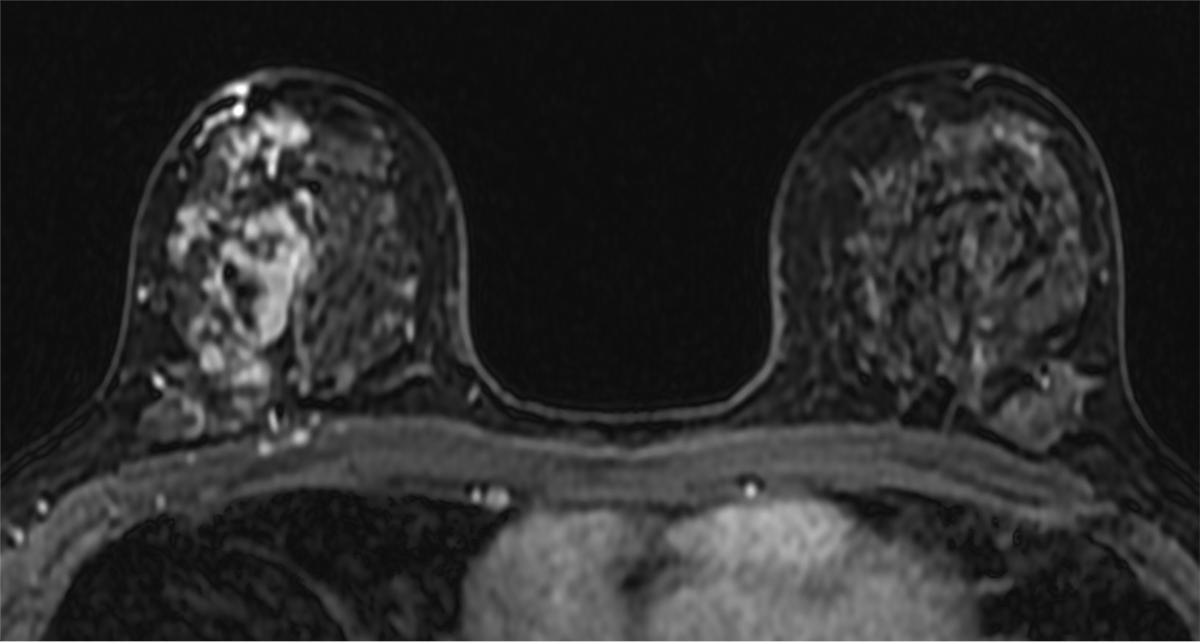

針生検の結果、ductal carcinoma in situ (DCIS)が疑われた。手術加療の方針となり、術前の広がり評価目的に造影MRIを撮像した。乳房全切除術及びセンチネルリンパ節生検を施行し、最終病理診断はDCISであった。

当該疾患の診断における造影MRIの役割

乳腺MRIは乳癌の広がりを高精度に診断できる。この症例においてもマンモグラフィーでは病変を指摘出来なかったが、MRIでは病変が明瞭に描出され、エコーで捉えられる領域よりも広範に及んでいる事が示された。3D解析を用いることでより俯瞰的な評価ができ、術式の選択や切除範囲の一助となった。

近年では、圧迫センシングなどの撮像技術の進歩によりUF-DCE MRIが可能となった。造影直後の超早期からの数秒毎の撮像を行うことで、乳腺組織とのコントラストを高め、血流豊富な腫瘍と腫瘍関連血管の評価に優れている。使用する造影剤量の増加や撮像時間の延長なく、良悪性の鑑別や薬物療法の治療効果予測に役立つと報告されており、更なる臨床応用が期待されている。